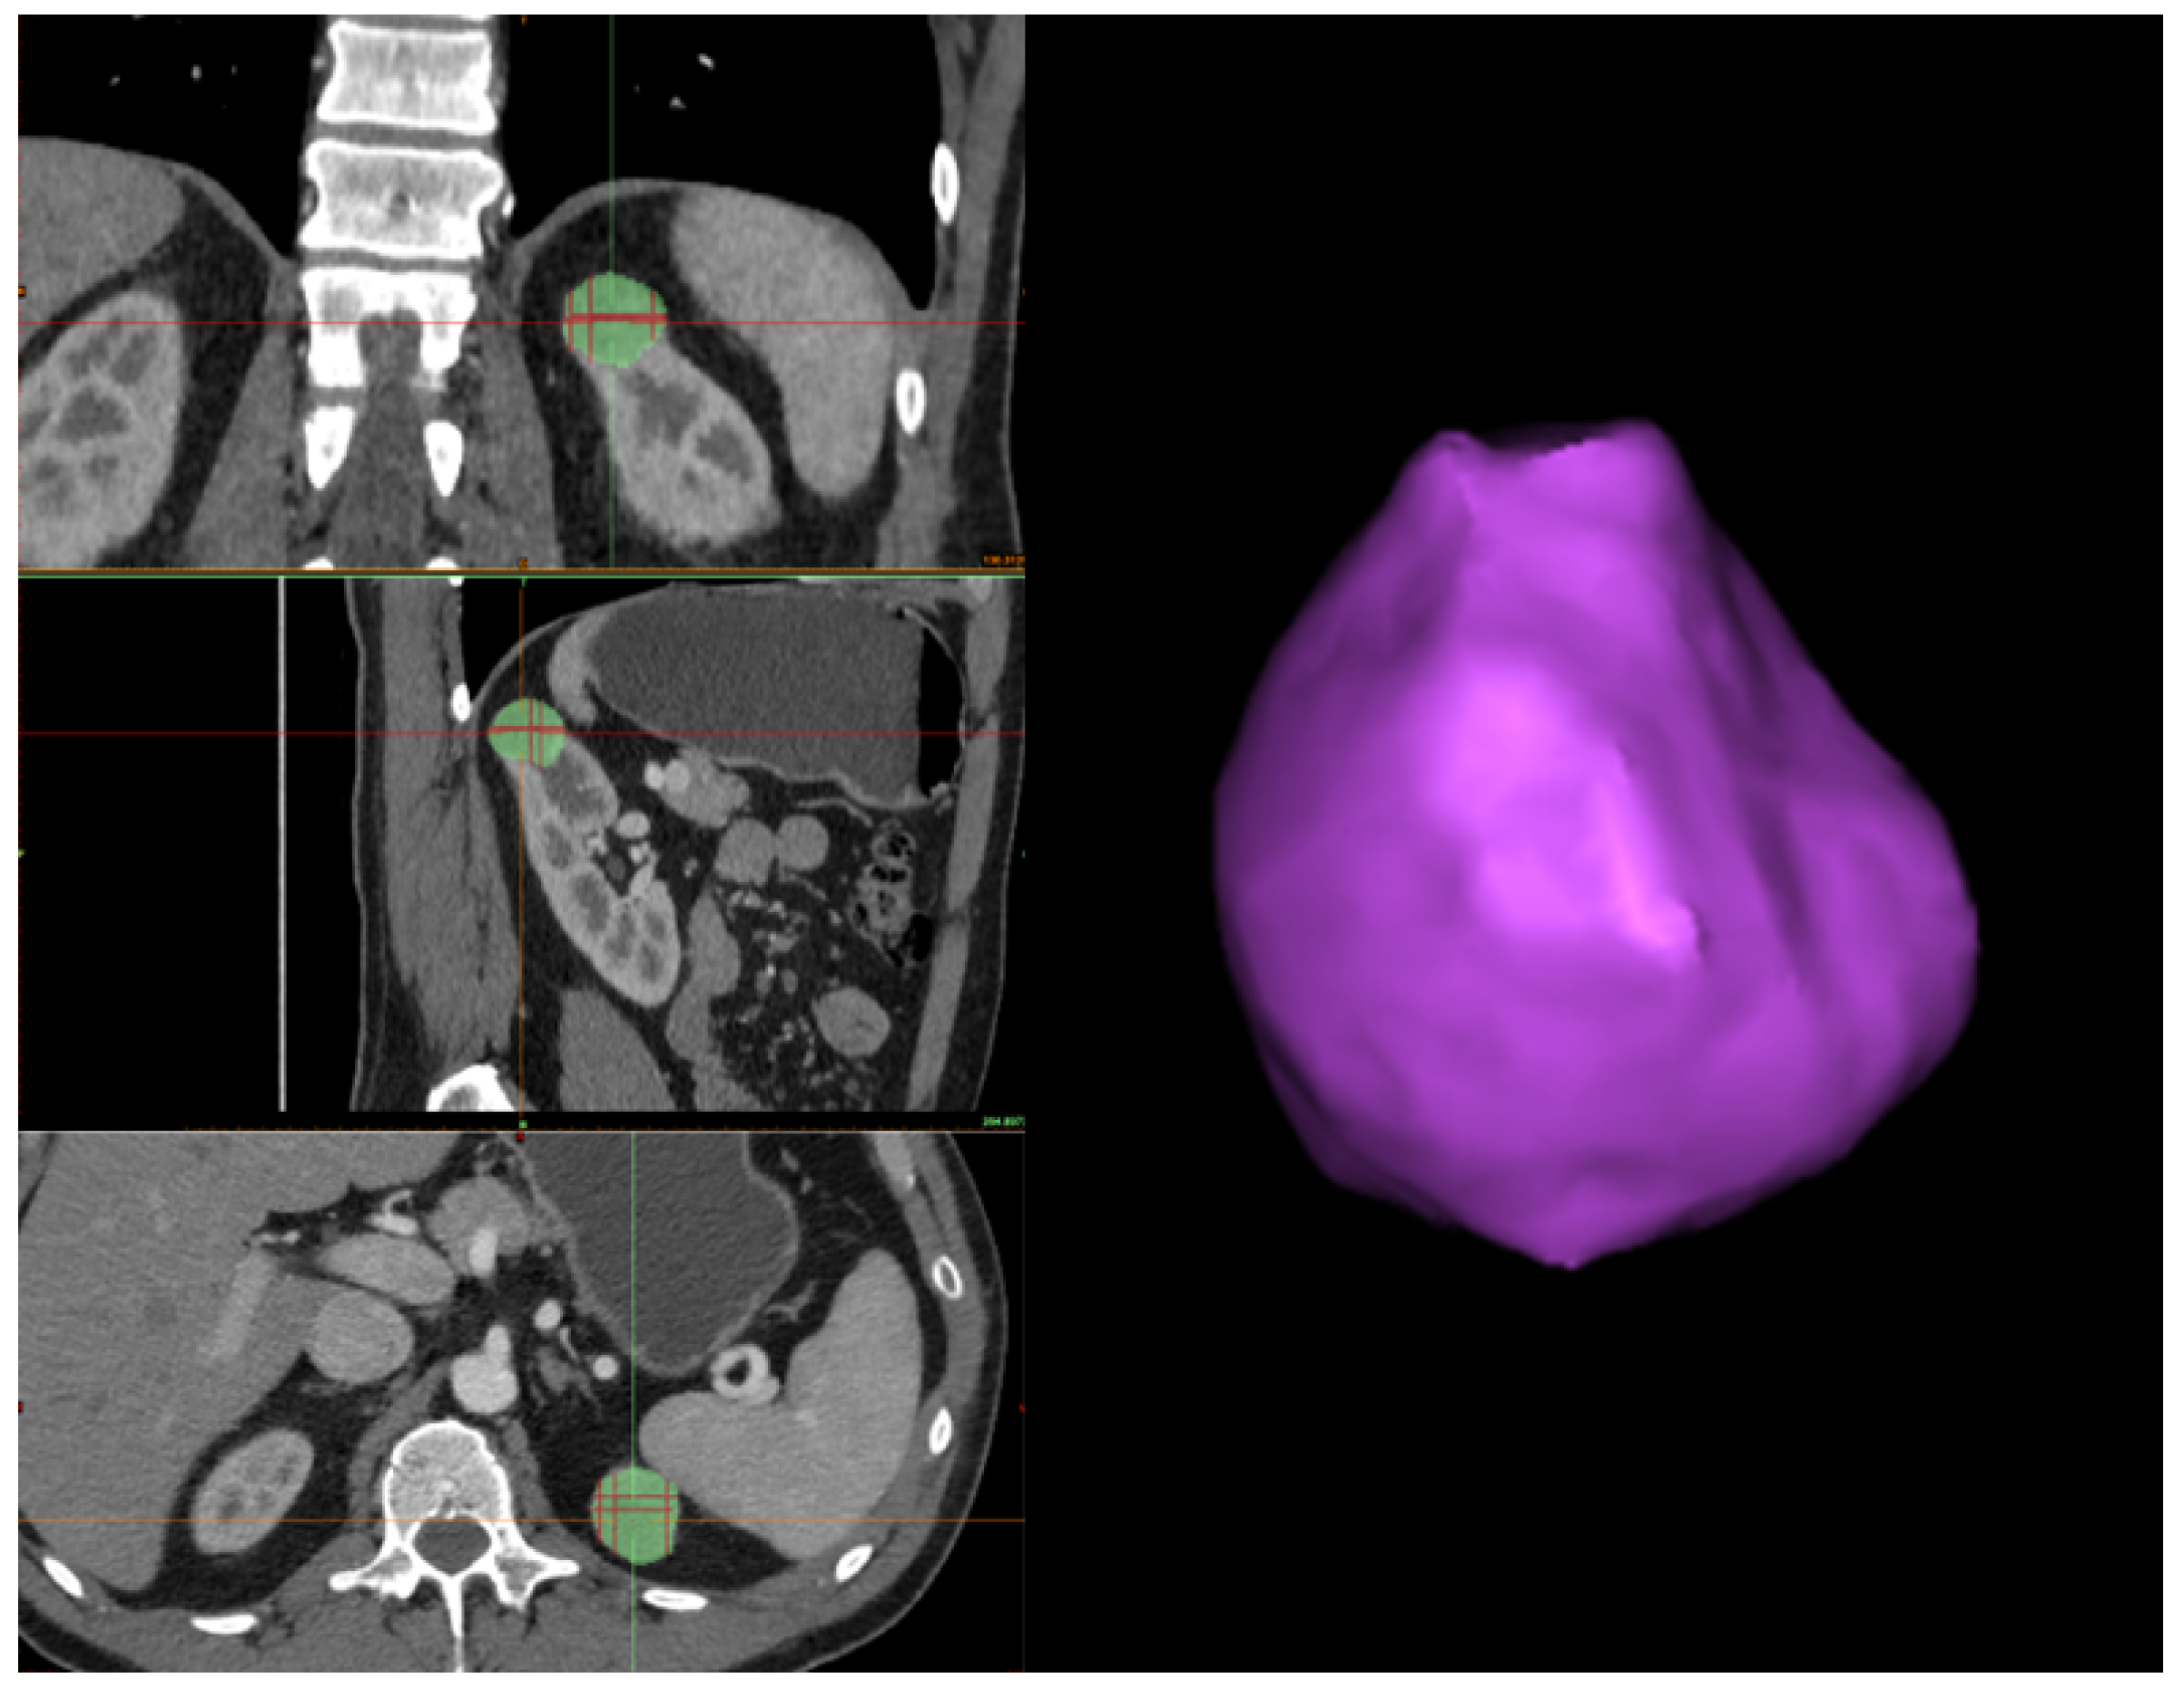

Tumor segmentation. In this stage, similar to kidney segmentation, a hybrid approach is employed, which encompasses semi-automatic processes executed through software tools and manual interventions performed by a human operator. Nevertheless, the segmentation process for tumors differs from that of kidneys. In this case, the tumor contour is directly outlined. Initially, the human operator must identify the tumor in all three sections (i.e., axial, coronal, and sagittal) from the CT scan. Subsequently, the tumor’s boundary must be outlined on each section using the 3D interpolate tool available in Materialise Mimics Inprint. Specifically, when delineating the tumor’s boundary, Materialize uses an algorithm that semi-automatically segments the tumor over the various slices and produces a 3D reconstruction of it, which may change depending on the selection of the tumor boundary in the next slice (see Figure 4).

Figure 4. On the left-hand side, the automated 3D interpolation of the tumor is shown based on the manually drawn silhouette in the three planes, where the green region represents the tumor in each plane. On the right-hand side is the 3D reconstruction of the tumor obtained from the interpolation of the three axes.